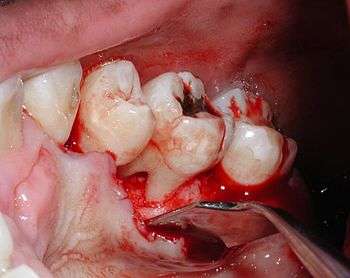

Furcation defect

In dentistry, a furcation defect is bone loss, usually a result of periodontal disease, affecting the base of the root trunk of a tooth where two or more roots meet (bifurcation or trifurcation). The extent and configuration of the defect are factors in both diagnosis and treatment planning.[1]

A tooth with a furcation defect typically possessed a more diminished prognosis owing to the difficulty of rendering the furcation area free from periodontal pathogens. For this reason, surgical periodontal treatment may be considered to either close the furcation defect with grafting procedures or allow greater access to the furcation defect for improved oral hygiene.